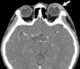

Lacrimal gland inflammation

The lacrimal glands are paired exocrine glands, one for each eye, found in most terrestrial vertebrates and some marine mammals, that secrete the aqueous layer of the tear film. In humans, they are situated in the upper lateral region of each orbit, in the lacrimal fossa of the orbit formed by the frontal bone. [Source: Wikipedia ]